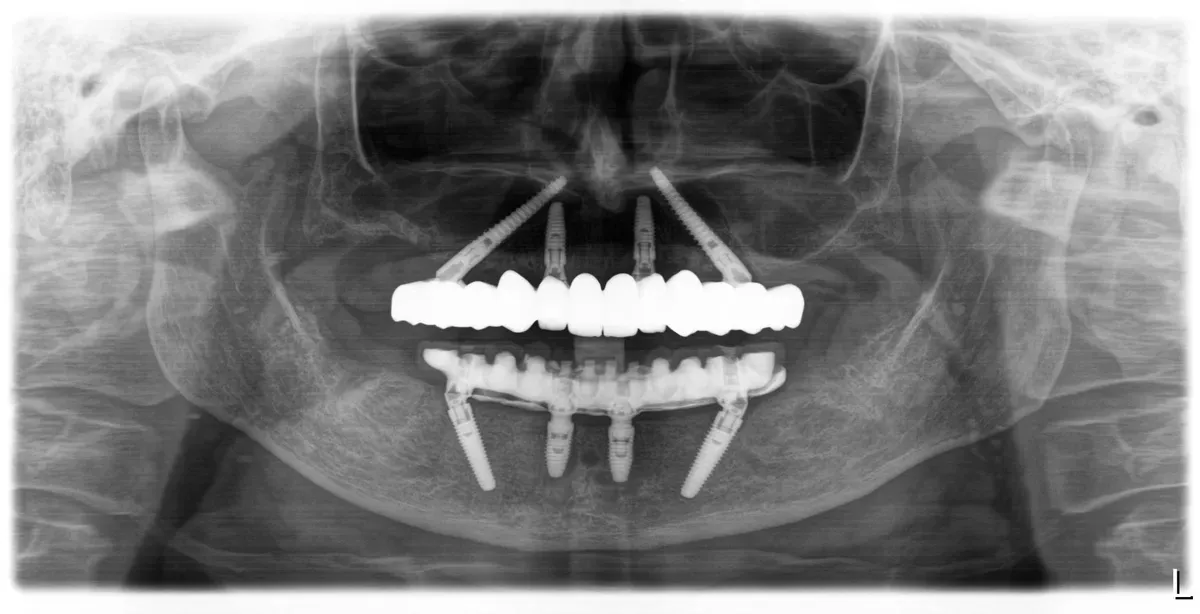

Dubravka G.

Pacijentica je došla u IMED zbog lošeg stanja u čeljusti, a nakon prvog pregleda preporučen joj je FP1 All-on-4 zahvat u gornjoj i donjoj čeljusti.

Zahvat je izveden u općoj anesteziji za maksimalnu udobnost i sigurnost pacijentice tijekom cijelog postupka, a nakon ugradnje implantata postavljen je trajni cirkonski rad bez umjetnog zubnog mesa u gornju čeljust, te metal-kompozitni rad u donju čeljust.

FP1 rješenje namijenjeno je pacijentima s dovoljno vlastite kosti u čeljusti te omogućuje iznimno prirodan izgled i vrhunsku funkcionalnost.